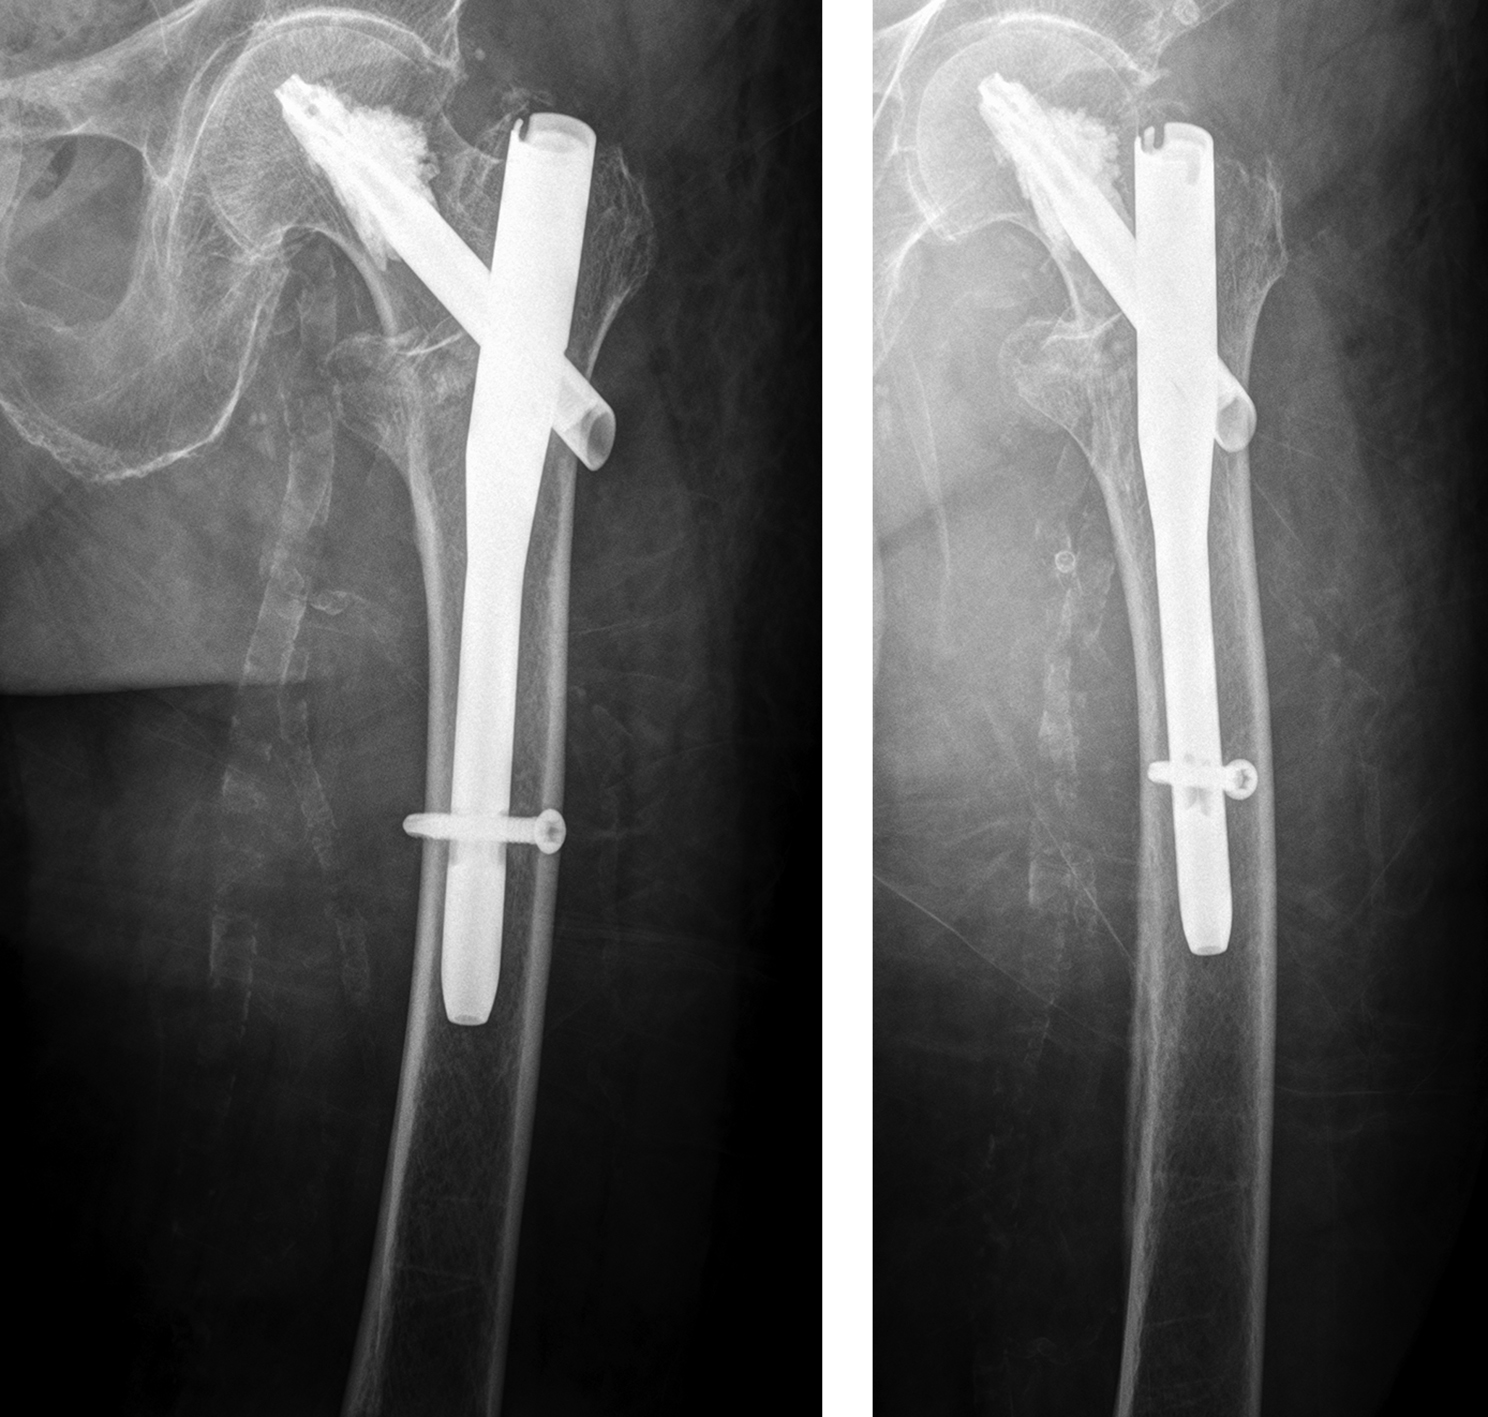

A 98-year-old female patient sustained a pertrochanteric fracture of the left proximal femur due to fall in her nursing home (Fig 1). There was significant pain and coxarthritis in the right hip, and hypertension. Surgery was performed within 24 hours. There was an indication for augmentation due to the instability of the fracture. The patient additionally suffered from osteoporosis and dementia.